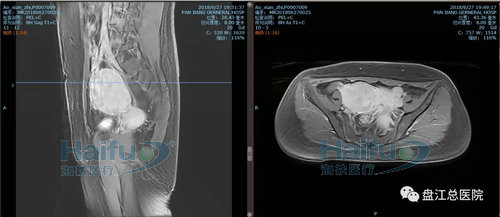

我院案例1:患者敖XX,44歲,多發性子宮肌瘤患者。

因經期延長1+月,發現盆腔包塊12+天入院。患者于2018-6-29在我院行高強度聚焦超聲消融治療(HIFU)。在鎮靜鎮痛狀態下,治療過程中未訴有特殊不適,安靜休息。本次治療時間70min。

術前后壁及右側壁肌瘤增強,見病灶明顯強化

術后后壁及右側壁肌瘤增強,見病灶內已無強化,病灶發生凝固性壞死